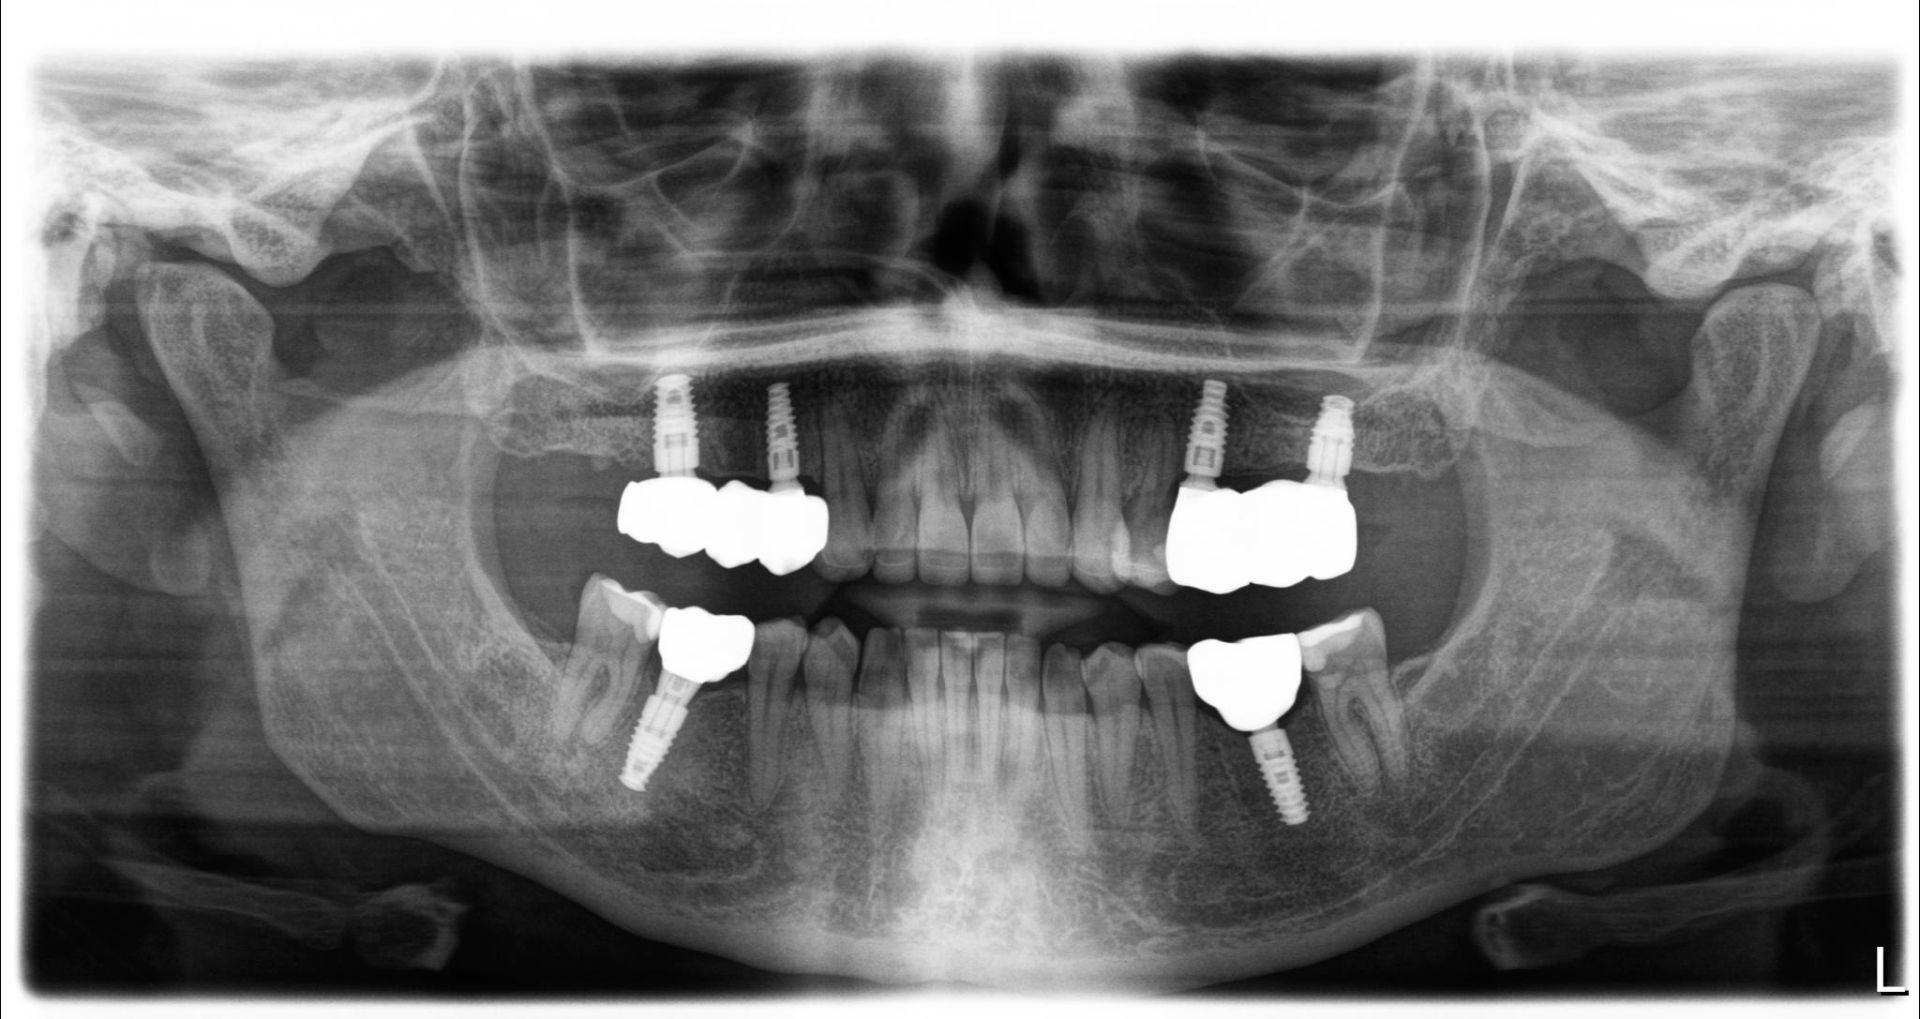

Before